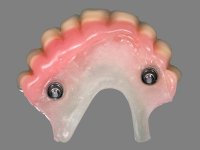

Após análise clínica e imagiológica foi proposto á paciente reabilitar o maxilar superior fazendo a colocação de 4 implantes e posteriormente ser reabilitada com uma Prótese Hibrida.Com a reabilitação proposta, também seria tentada a correção prostodontica da falta de apoio do lábio superior, desde que aprovada esteticamente pela paciente após um “Mock-up” prévio.

Inicialmente foram confecionadas duas novas próteses removíveis. O dente 1.3 foi extraído quando da colocação das próteses. Feito o estudo imagiológico necessário, foram colocados 4 implantes no maxilar superior. Após 3 meses de osteointegração foi feita a impressão para a confeção de ceras de articulação montadas em placa base aparafusadas aos implantes. Estas ceras foram utilizadas na recolha das relações inter-maxilares e na tentativa de proporcionar apoio ao lábio superior. Foi feita a prova de dentes com estes montados em placas base aparafusadas permitindo uma avaliação estética dinâmica muito interessante. Sendo validada esteticamente pela paciente, esta prova deu origem a uma muralha de silicone que orientou laboratorialmente a confeção da infraestrutura metálica. A infraestrutura metálica com os dentes montados em cera foi provada em boca, permitindo simultaneamente verificar a sua adaptação bem como a estética final. O trabalho final foi colocado em boca sendo acompanhado de instruções rigorosas de técnicas de higiene oral bem como da informação da necessidade de consultas de controlo periódicas.